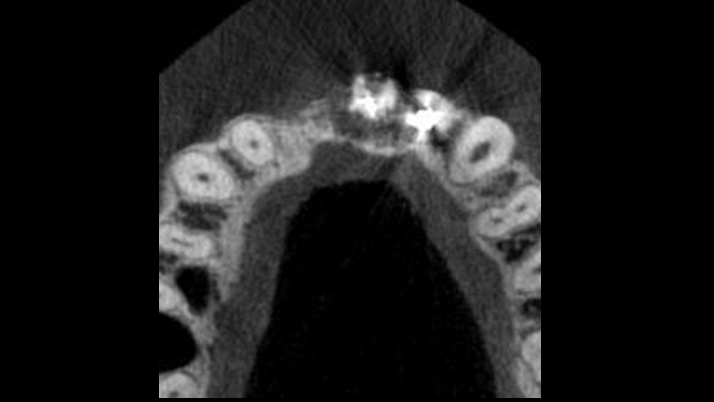

Clinical case: Patient-centered approach: treatment strategy for Root Membrane Technique & delayed implant placement

- Courtesy of Dr. Yoshiharu Hayashi, Japan -

Socket Shield Technique, anterior esthetics, maxillary anterior, esthetic, esthetics, delayed implant placement, socket preservation, AnyRidge, Root Membrane Kit, Root Membrane Technique, Partial Extraction Therapy, PET, esthetic zone, fuse abutment, Dr. Yoshiharu Hayashi,#11,#21,#22

AnyRidge implant system, fuse abutment Root membrane kit, PET Kit